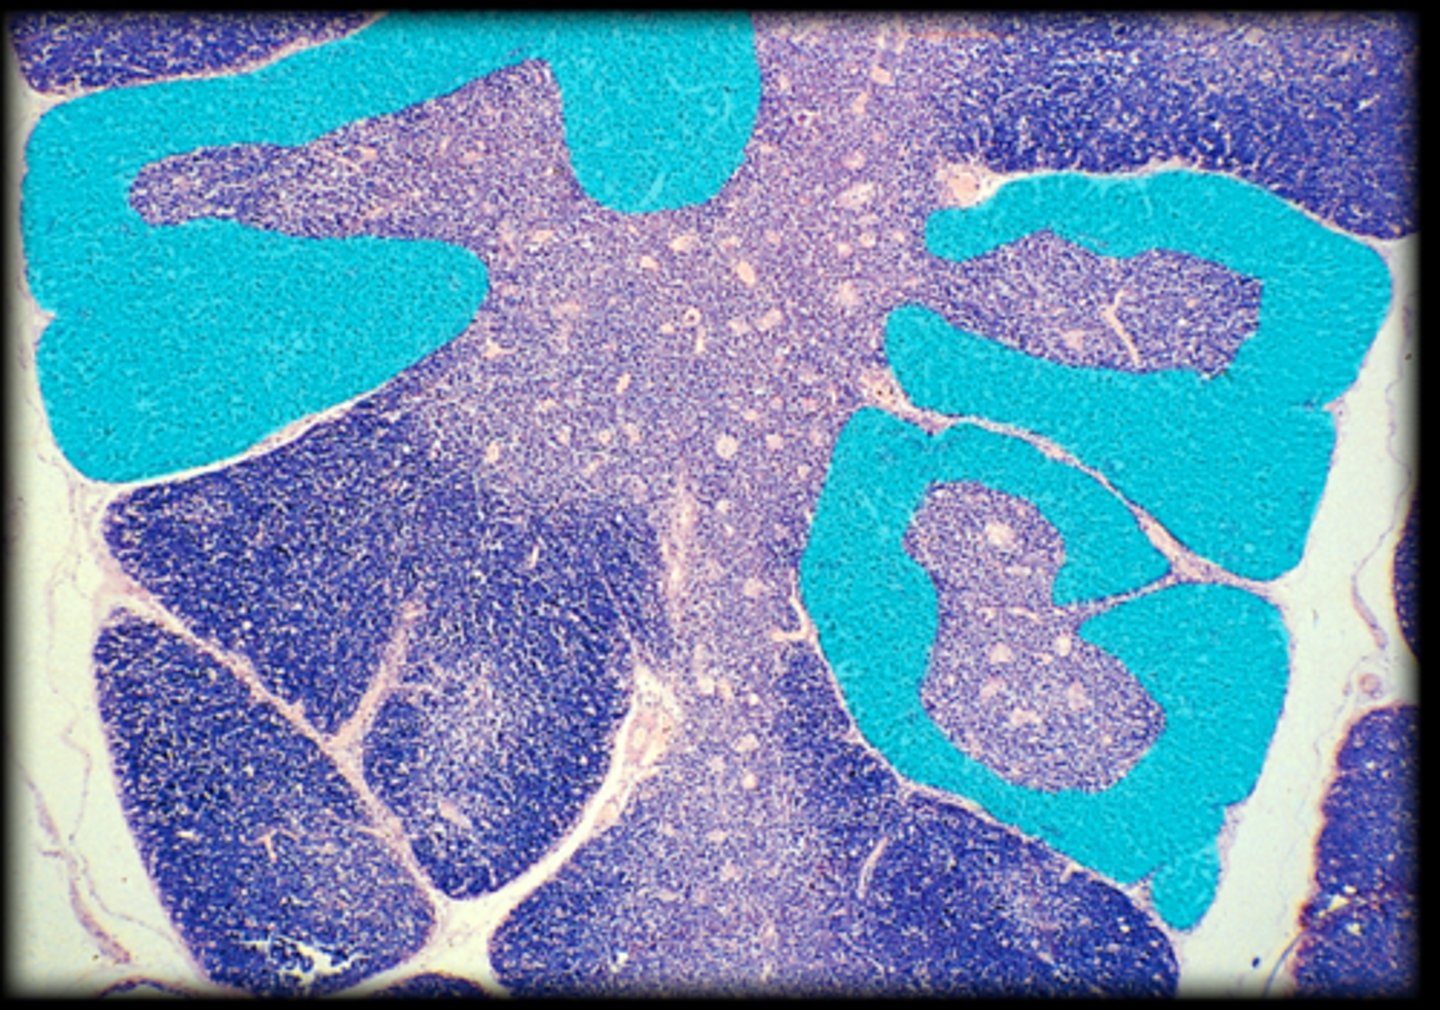

central white pulp

Spleen

red pulp

white pulp